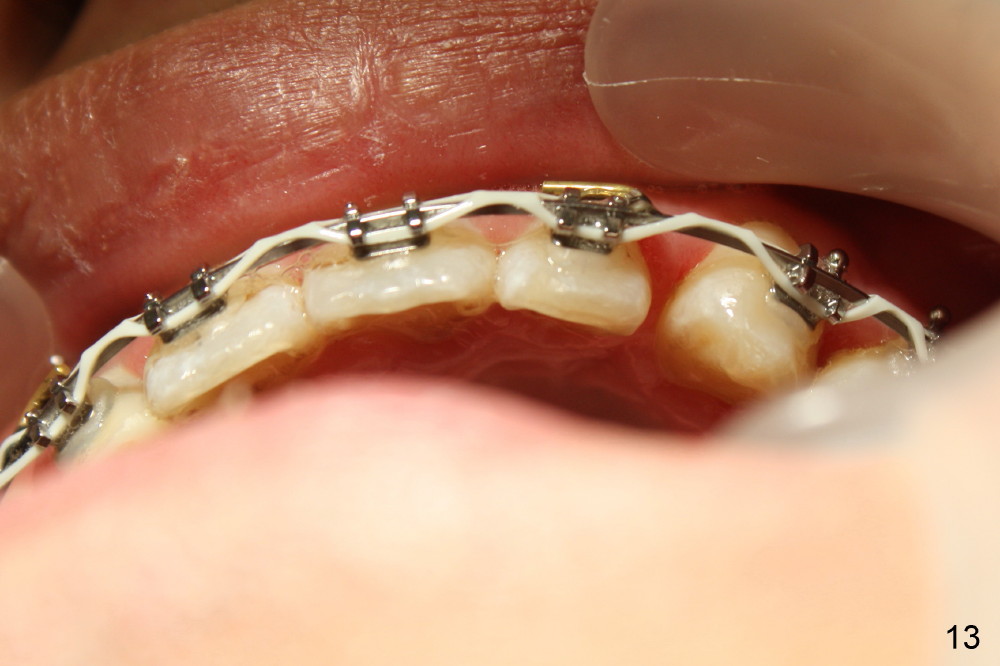

Fig.13-15 shows the upper incisors totally 4.5 month of retraction. The upper left canine (Fig.15: #11) seems to be distalized too much, as compared to the dashed line. Therefore whole arch power chain is placed with an intention to bring the canine mesially (arrowhead) while continue distalizing the incisors (including #10 (arrowhead).